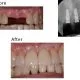

case-studies Case #4 Patient had a periodontal infection and lost his front tooth. It was removed and restored with an implant-supported ceramic crown.February 25, 2024/by Rich https://sunnyvaledentalspecialty.com/wp-content/uploads/2018/08/Untitled-1.jpg 527 551 Rich https://sunnyvaledentalspecialty.com/wp-content/uploads/2017/03/logo.png Rich2024-02-25 12:32:002024-05-02 11:09:54Case #4